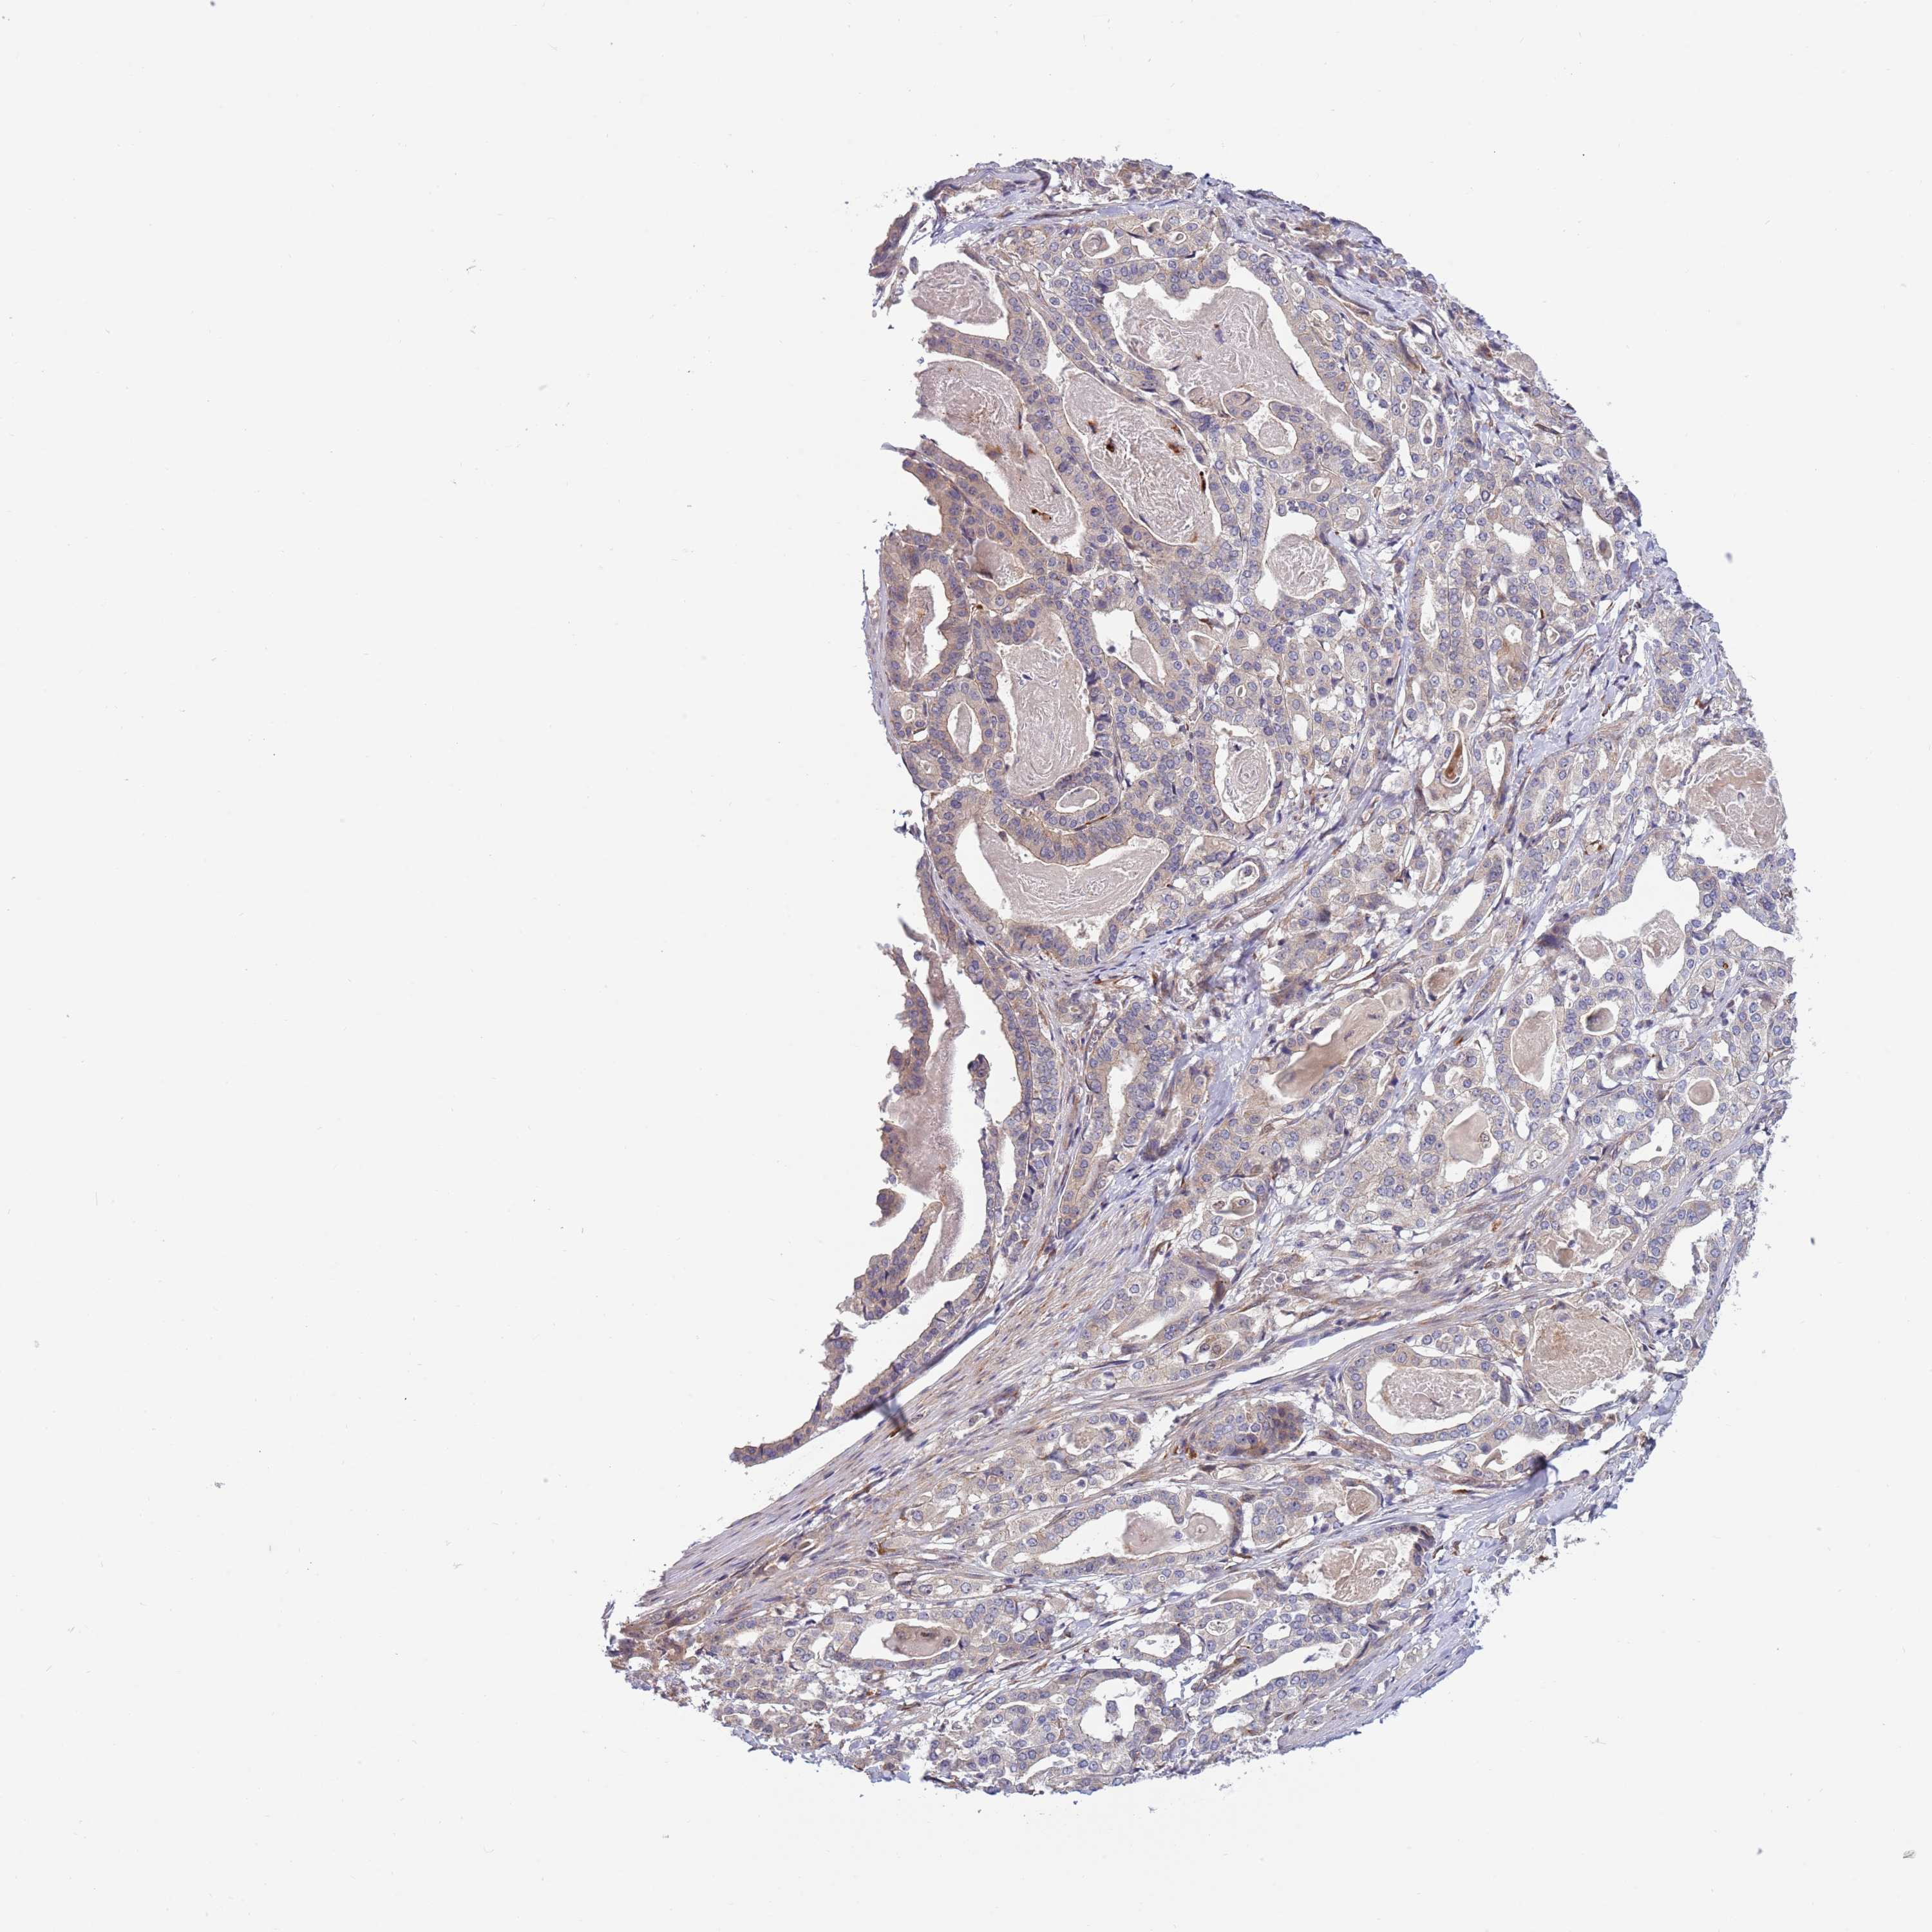

STOMACH CANCER - Protein expressioni

A mouse-over function shows sample information and annotation data. Click on an image to view it in a full screen mode. Samples can be filtered based on level of antibody staining by selecting one or several of the following categories: high, medium, low and not detected. The assay and annotation is described here.

Note that samples used for immunohistochemistry by the Human Protein Atlas do not correspond to samples in the TCGA dataset.

Antibody stainingi

Antibody staining in the annotated cell types in the current human tissue is reported as not detected, low, medium, or high, based on conventional immunohistochemistry profiling in selected tissues. This score is based on the combination of the staining intensity and fraction of stained cells.

Each image is clickable and will lead to virtual microscopy that enables deeper exploration of all samples and also displays staining intensity scores, fraction scores and subcellular localization as well as patient and tissue information for each sample.

Antibody HPA047881

Staining

High

Medium

Low

Not detected

Intensity

Strong

Moderate

Weak

Negative

Quantity

>75%

75%-25%

<25%

None

Location

Nuclear

Cytoplasmic/membranous

Cytoplasmic/membranous,nuclear

Adenocarcinoma, NOS